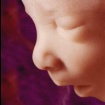

8. týden